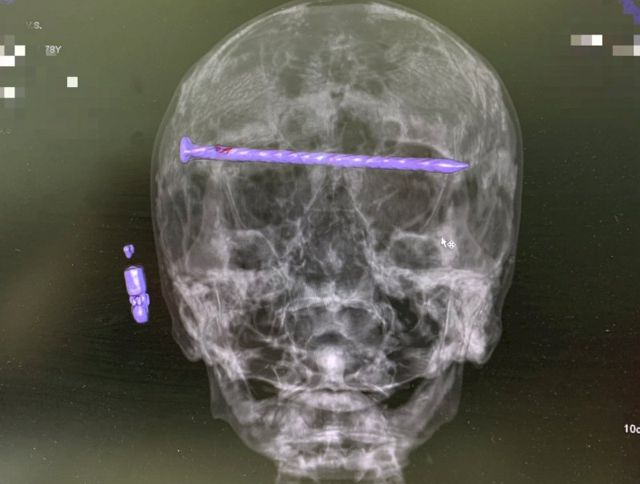

Свердловские врачи сумели вынуть из головы жителя Нижнего Тагила 15-сантиметровый гвоздь, который прошел от виска к виску, задев оба глаза. Медики сумели также сохранить пациенту зрение, сообщает департамент информационной политики региона.

В результате бытовой травмы в черепе 78-летнего тагильчанина оказался гвоздь, который прошел через обе глазницы от правого до левого виска. Ситуация осложнялась повреждением твердой оболочки мозга и сдавлением глазных яблок. Медики во главе с заведующим нейрохирургическим отделением ГБ № 1 Нижнего Тагила Дмитрием Неволиным провели сложную операцию, сумев вынуть гвоздь, а также сохранить зрение и целостность черепа пациенту.